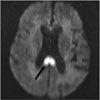

MRI scans of the head revealed acute infarcts (arrows) in the right corona radiata, right centrum semiovale, and anterior and posterior corpus callosum.

In this patient, the syndrome manifested by her left hand can be attributed to the posterior callosal infarct, while the grasping nature of her dominant right “alien” hand may result from a new anterior callosal infarct combined with the prior parietal lobe infarct. Despite the association of this syndrome with Alzheimer- type dementia, we believe our patient's condition was related to the new infarcts.